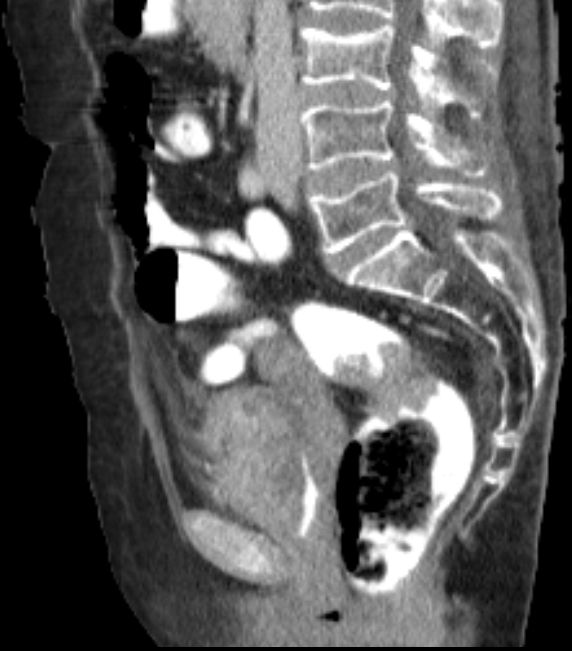

| T4-Tumor | 67-jährige demente Frau mit T4-Blasentumor

(invasives Urothelkarzinom) und Rektumkarzinom.![]() |

![]() |

![]() | |